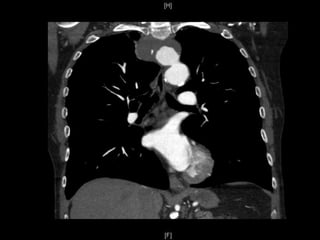

Suites Post-operatoires: CTA

 Aucunes

endofuites ou

migration

 Exclusion

complete et

thrombose de

artere lusorienne

ainsi que le

diverticule

Cas1

 Aucunes complications post-operatoire

 Duree hospitaliere:

 6 jours

 Suite post-opératoire:

 Asymptomatique (resolution de la toux)

 CTA a 4 mois post TEVAR